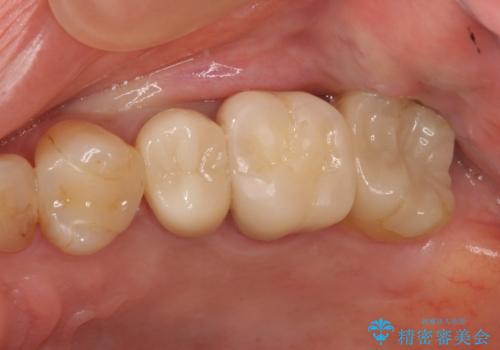

奥の銀歯のやりかえも希望されたため、セラミッククラウン、インレーにする治療をしています。

- 合計 48.4万円( 左上5:再根管治療 9万円、ファイバーコア2万円、仮歯1万円、ジルコニアクラウン10万円 左上6:仮歯、ジルコニアクラウン 左上7:emaxインレー7万円)費用は治療当時の料金となります

左上6番のアンレーは、歯の破折を防ぐためにクラウンとしました。